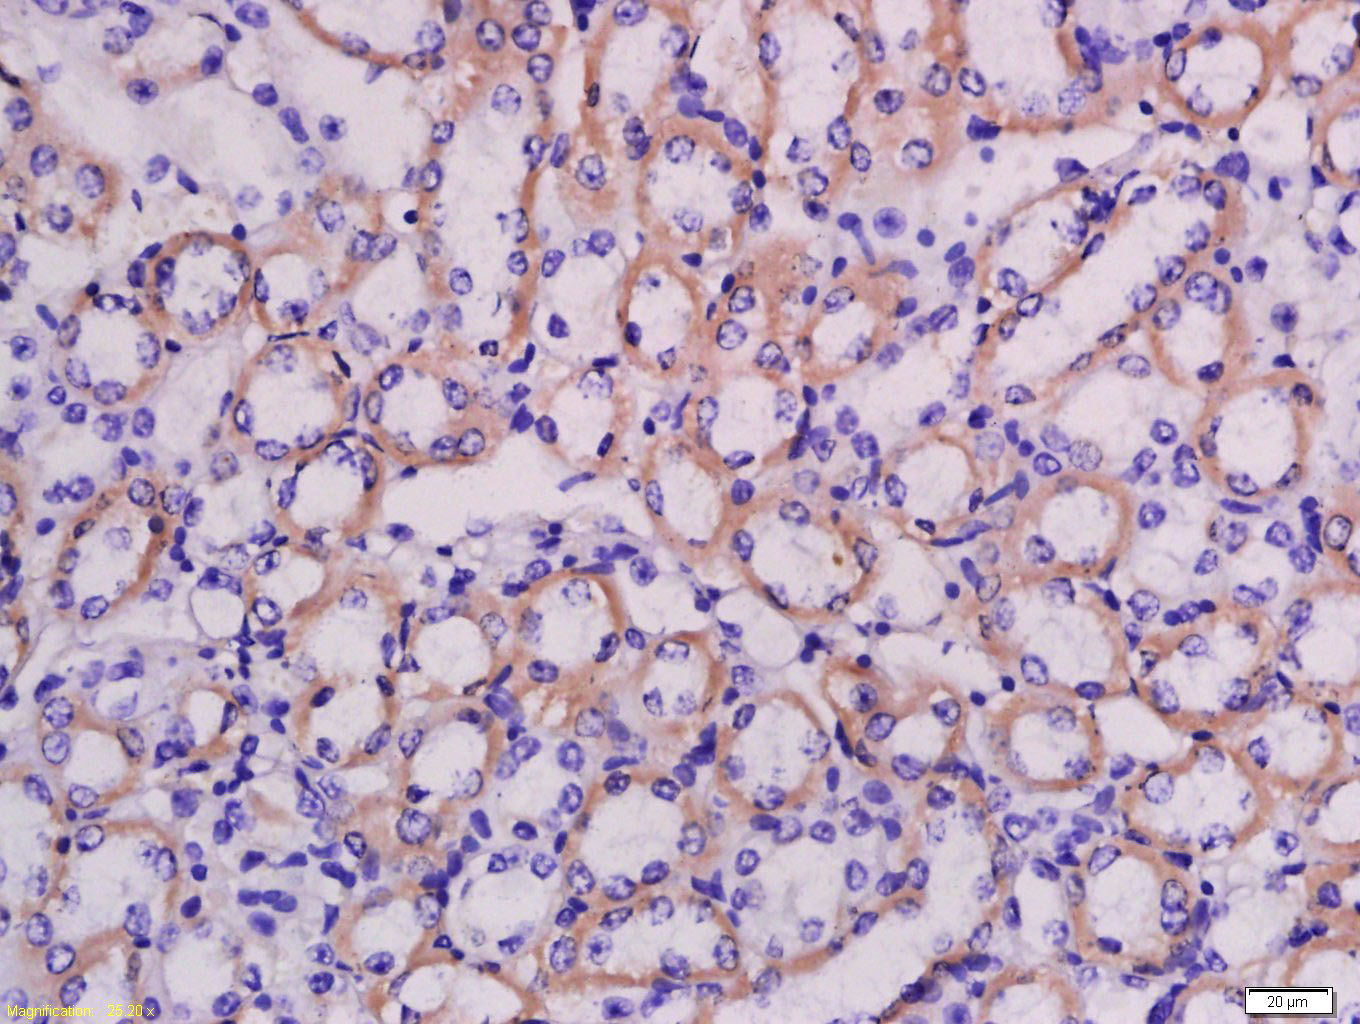

Tissue/cell: mouse kidney tissue; 4% Paraformaldehyde-fixed and paraffin-embedded; Antigen retrieval: citrate buffer ( 0.01M, pH 6.0 ), Boiling bathing for 15min; Block endogenous peroxidase by 3% Hydrogen peroxide for 30min; Blocking buffer (normal goat serum,C-0005) at 37℃ for 20 min; Incubation: Anti-LRRC67 Polyclonal Antibody, Unconjugated(bs-18400R) 1:200, overnight at 4°C, followed by conjugation to the secondary antibody(SP-0023) and DAB(C-0010) staining